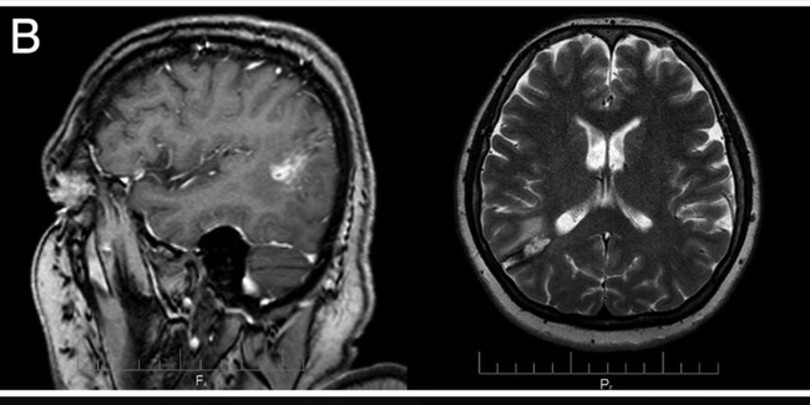

საქართველოში ქალის ტვინიდან 15-სანტიმეტრიანი ცოცხალი პარაზიტი Taenia solium, ანუ ღორის სოლიტერი, ამოიყვანეს. ქართველმა ქირურგებმა ეს შემთხვევა დეტალურად აღწერეს, მათი ნაშრომი კი ახლახან რეფერირებად გამოცემაში Journal of Neurosurgery გამოქვეყნდა.

ონკოლოგიური ისტორიის მქონე 54 წლის ქალი ქირურგებთან ტვინის სიმსივნის დიაგნოზით მივიდა. ამოკვეთის მცდელობისას ექიმებმა ტვინში 15-სანტიმეტრიანი ცოცხალი ჭია შენიშნეს.

ამოყვანილი ჭია შემდგომში პარაზიტოლოგიის ინსტიტუტმა შეისწავლა. დადასტურდა, რომ ქალს ტვინში მართლაც ზრდასრული თასმისებური ჭია, T. solium, ჰყავდა. ტვინის ქსოვილის მიკროსკოპული კვლევით თასმისებური ჭიის კვერცხებიც შენიშნეს, რომლებიც განვითარების სხვადასხვა სტადიაზე იყო; მათ სპეციფიკური სქელი, ზოლიანი გარსები ჰქონდა.

ოპერაციიდან რამდენიმე თვის განმავლობაში ქირურგები შემთხვევის შესწავლასა და აღწერაზე მუშაობდნენ. ნაშრომმა რეცენზირება გაიარა და რეფერირებად სამეცნიერო ჟურნალში გამოქვეყნდა. გამოდის, სამეცნიერო ლიტერატურაში ეს პირველი დადასტურებული შემთხვევაა, როცა ადამიანის თავის ტვინში ზრდასრული ღორის სოლიტერი დაფიქსირდა.

წაიკითხეთ ვრცლად: ადამიანის ტვინში ზრდასრული ღორის სოლიტერი პირველად დაფიქსირდა და ეს საქართველოში მოხდა